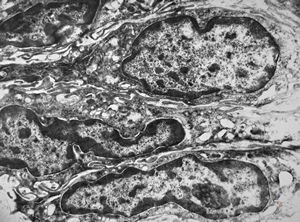

F,41y. | synovial metaplasia - capsule of implantate

F,41y. | synovial metaplasia - capsule of implantate

F,41y. | synovial metaplasia - capsule of implantate

F,41y. | synovial metaplasia - capsule of implantate

F,41y. | synovial metaplasia - capsule of implantate

F,41y. | synovial metaplasia - capsule of implantate

F,41y. | synovial metaplasia - capsule of implantate

F,41y. | synovial metaplasia - capsule of implantate

F,41y. | synovial metaplasia - capsule of implantate